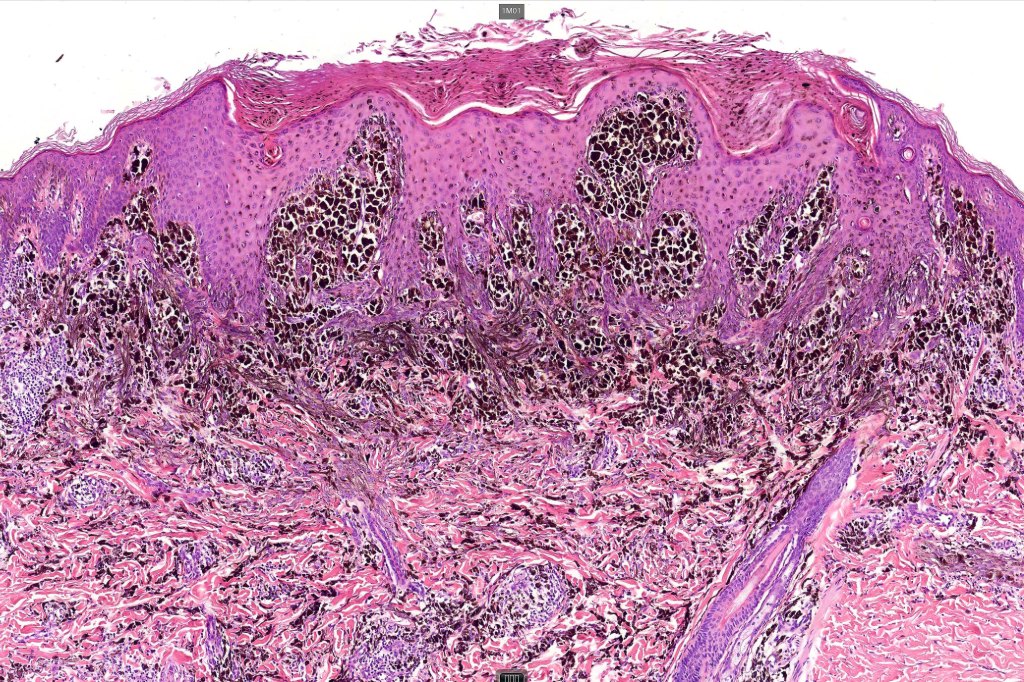

•Dermal of less often compound

•Wedge shape or less often plaque like silhouette

•Commonly associated with marked acanthosis/pseudoepitheliomatous hyperplasia although much less commonly, the epidermis is strteched over the lesion

•Composed of an admixture of large epithelioid melanocytes with vesicular nuclei containing a very prominent nucleolus (fried egg cells), spindle cells, dendritic cells & melanophages